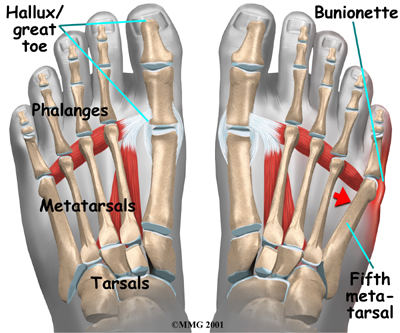

A bunionette is similar to a bunion, but it develops on the outside of the foot. It is sometimes referred to as a tailor's bunion because tailors once sat cross-legged all day with the outside edge of their feet rubbing on the ground. This produced a pressure area and callus at the bottom of the fifth toe.

A bunionette occurs over the area of the foot . This area is called the metatarsophalangeal joint, or MTP joint. The metatarsals are the long bones of the foot. The phalanges are the small bones in each toe. The big toe has two phalanges, and the other toes have three phalanges each.

Today a bunionette is most likely caused by an abnormal bump over the end of the fifth metatarsal (the metatarsal head) rubbing on shoes that are too narrow. Some people's feet widen as they grow older, until the foot splays. This can cause a bunion on one side of the foot and a bunionette on the other if they continue to wear shoes that are too narrow. The constant pressure produces a callus and a thickening of the tissues over the bump, leading to a painful knob on the outside of the foot.